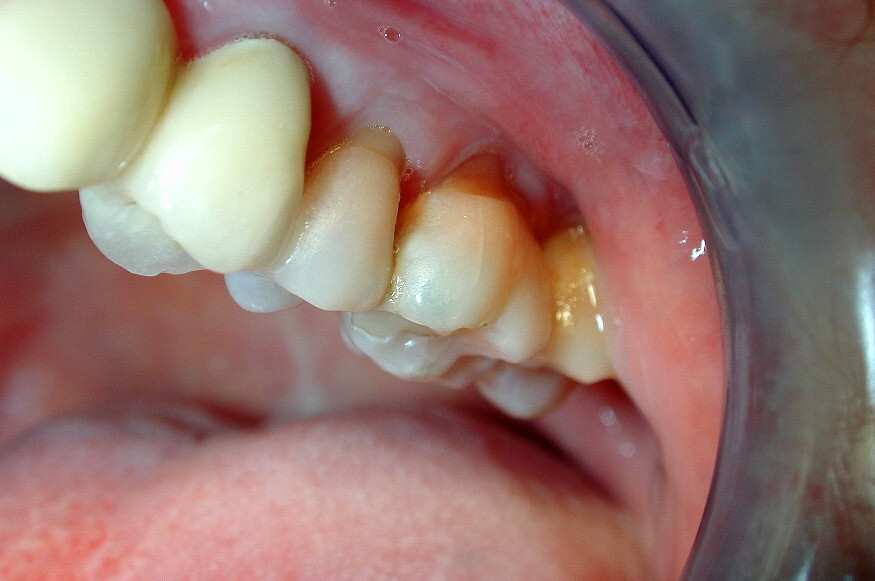

Resorption occurs any time a part of the body gets absorbed into another part of the body. When we talk about tooth resorption, we generally mean the inflammation and loss of dentin (the inner tissue of the tooth) and cementum (the outer tissue of the tooth) due to absorption. Root resorption specifically refers to when the roots of a tooth or teeth get absorbed into the gums and jaw.

Root resorption is a natural part of the body’s way of recycling old tooth and bone material, and the process of the body eating away at the roots of a tooth are a natural part of losing baby teeth. But when the body starts to absorb material from the roots of permanent teeth, that’s a problem.

Root resorption in adult teeth is usually a result of some sort of trauma to the teeth, often caused by forced shifting of the teeth. This can happen after someone suffers a blow to that tooth, such as in a high-impact sport, but it can also happen as a result of orthodontic treatment.

When we wear braces, the teeth are being pushed and pulled into alignment to produce a healthier bite. Ideally, the bone should be remodeled to accommodate the new position of the teeth, but if the shift happens too quickly, the bone might not have time to readjust, leaving the roots of the teeth to decay and be absorbed back into the rest of the body. If the roots dissolve too much, they could loosen in the gums and even fall out.